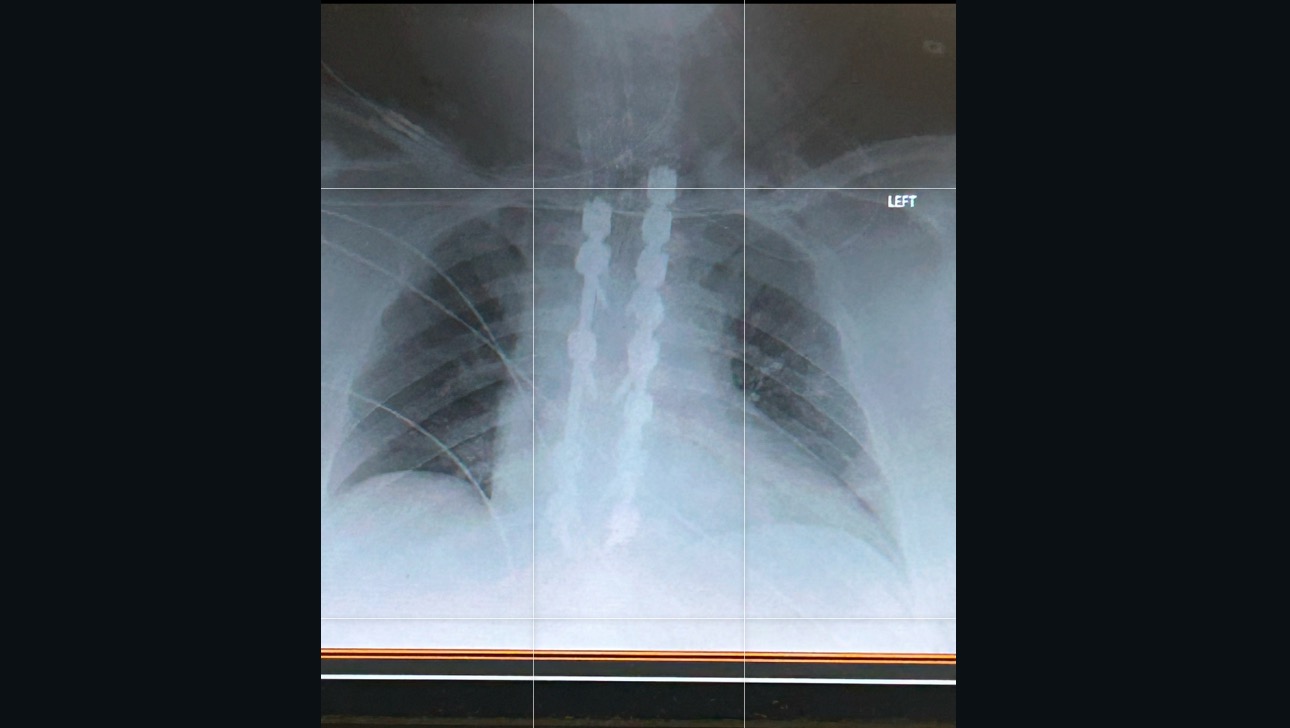

Hello, I’m Melanie! I’m making this for my brother Roman. He has a condition called Spinal Stenosis that came on fast and suddenly. He just recently got surgery and they replaced half of his spine. He currently can’t walk or feel his legs. He now has a 30% chance to be able to walk again and it could take years till he can. We need help to pay for other medical bills that insurance will not cover and for rehabilitation hospital, physical therapy and after caregivers. Any help we can get for him Is greatly appreciated, thank you!